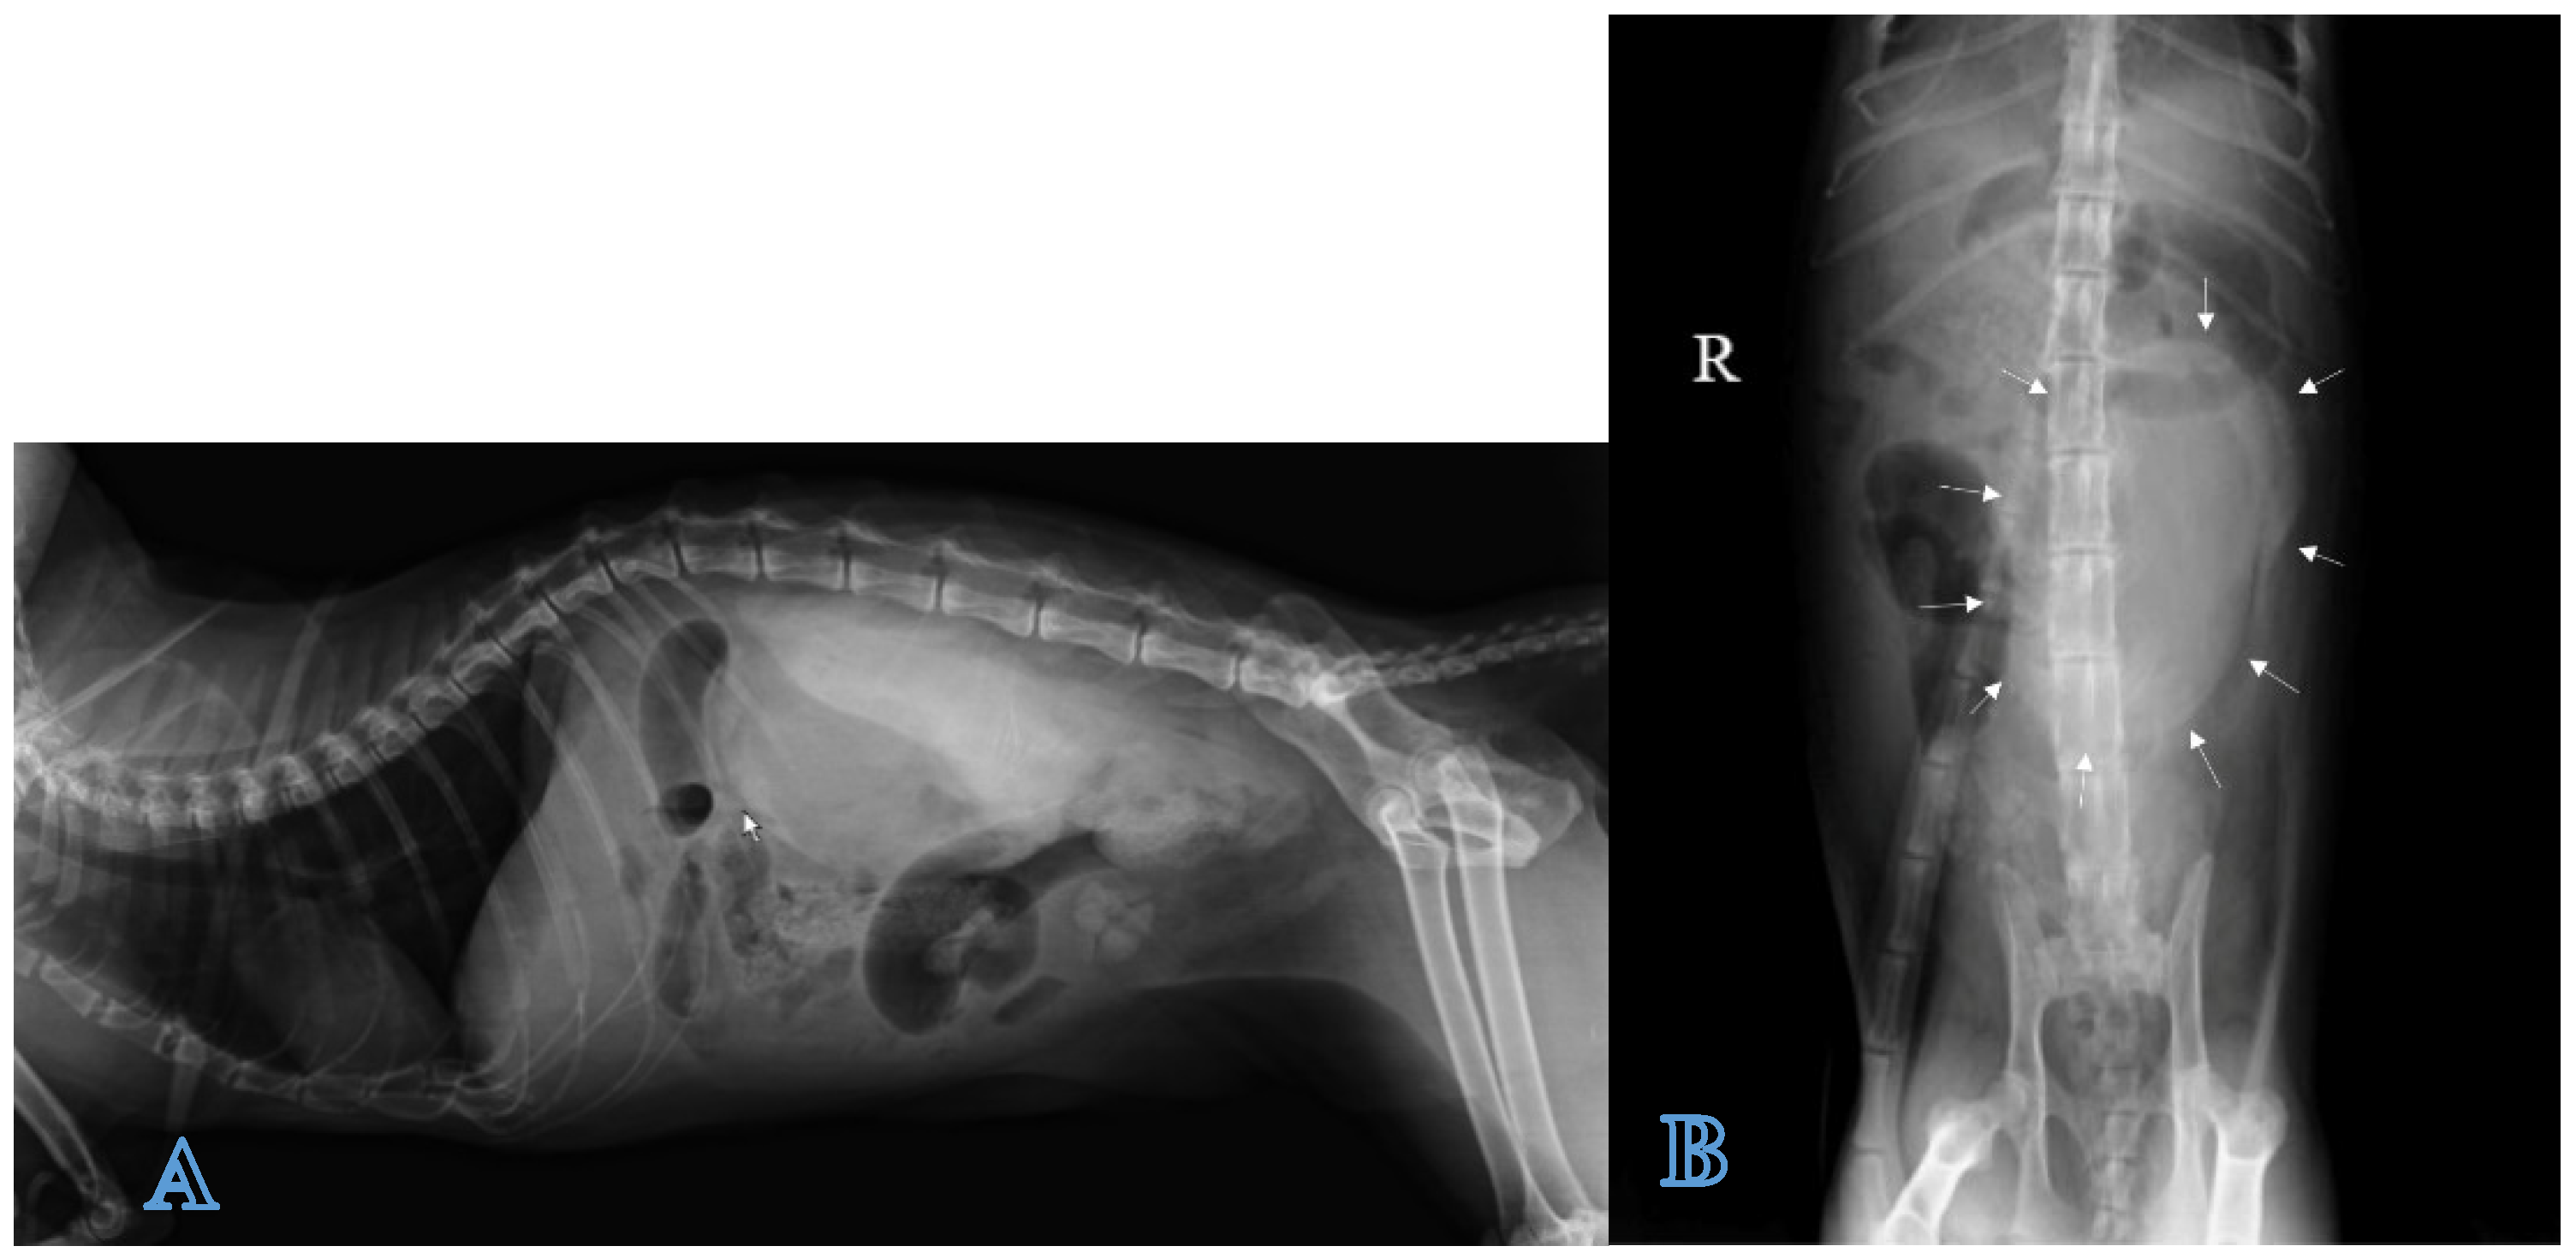

Positive contrast radiographs in the lateral and ventrodorsal projections immediately after the injection of the contrast agent allowed for defining the extent of the lesion, outlining the fluid collection as a large well-marginated homogeneous radiopaque area in the left retroperitoneal space and differentiating it from ascite (Figure 5A,B).

Figure 5.

Positive contrast X-ray exam of the abdomen: (A) Left lateral and (B) ventrodorsal projections. Contrast medium that borders the fluid collection is shown in arrows.